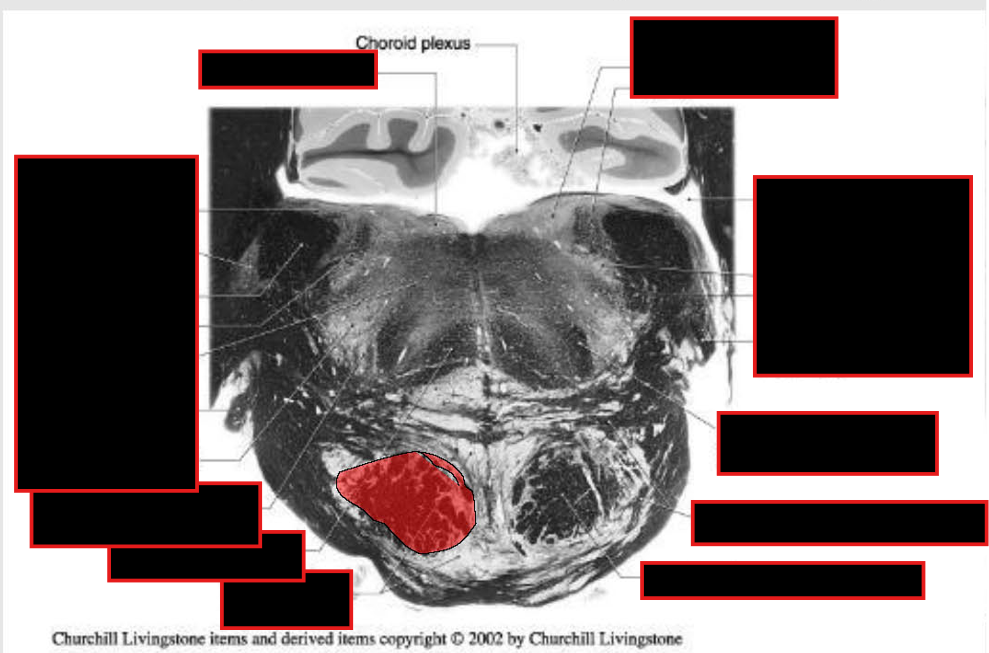

location of major tracts in the Caudal Pons:

CST/corticonuclear (bulbar) run through the substance of the basilar pons

Medial Lemniscus:

still in the midline

begins to turn → somatotopy shifts → leg areas = more lateral

anterolateral system

still in lateral position w/in pontine tegmentum,

@ anterolateral edge w/ formation of middle cerebellar peduncle.

Rubrospinal Tract:

Dorsal to ALS

Reticulospinals and vestibulospinals

still being formed in this area, so they are not clear.

spinal nucleus and tract of CN V

still present as pars oralis

just dorsal to the exit of the facial nerve.

MLF and tectospinal (tectobulbospinal ) tracts

dorsal position near the midline.

will now carry motor information for eye movements.

Other Ascending/Descending → displaced into the pontine tegmentum